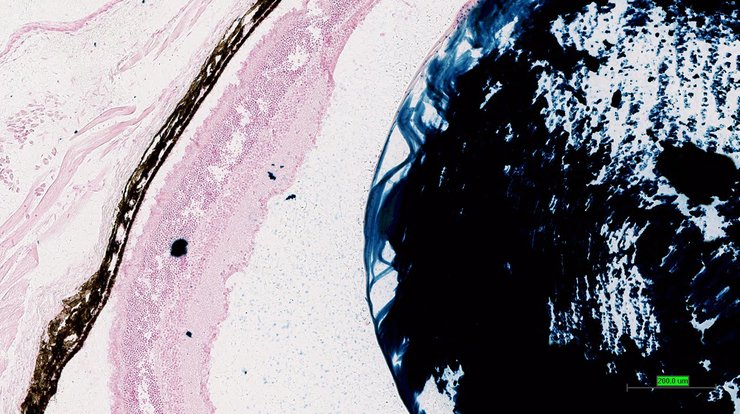

TS28: eye Present UC Davis_1888857

TS28: eye Present UC Davis_1888858

TS28: eye Present UC Davis_1888859